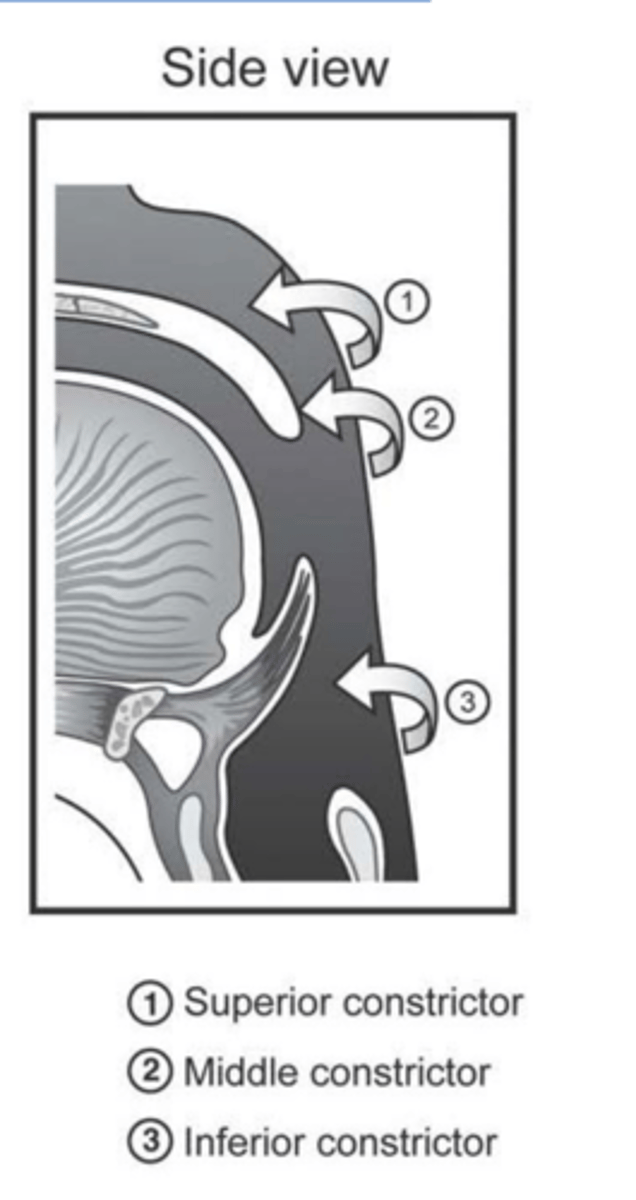

3 pairs of muscles, referred to as constrictors

Action of each is to reduce the diameter of a portion of the pharyngeal cavity

Superior Constrictor Description

Weakest, but most complex of the three

Forms nasopharyngeal and upper

oropharyngeal walls

Origin - sphenoid, mandible, pterygomandibular ligament

Course - posterior, then medial

Insertion - midline raphe

Action - may contribute to velopharyngeal closure by moving posterior wall of pharynx

anteriorly

Superior Constrictor Figure

Middle Constrictor Description

Somewhat fan shaped

Origin - hyoid bone

Course - fan out posteriorly and medially

Insertion - midline raphe

Action - reduce diameter of pharynx

Middle Constrictor Figure